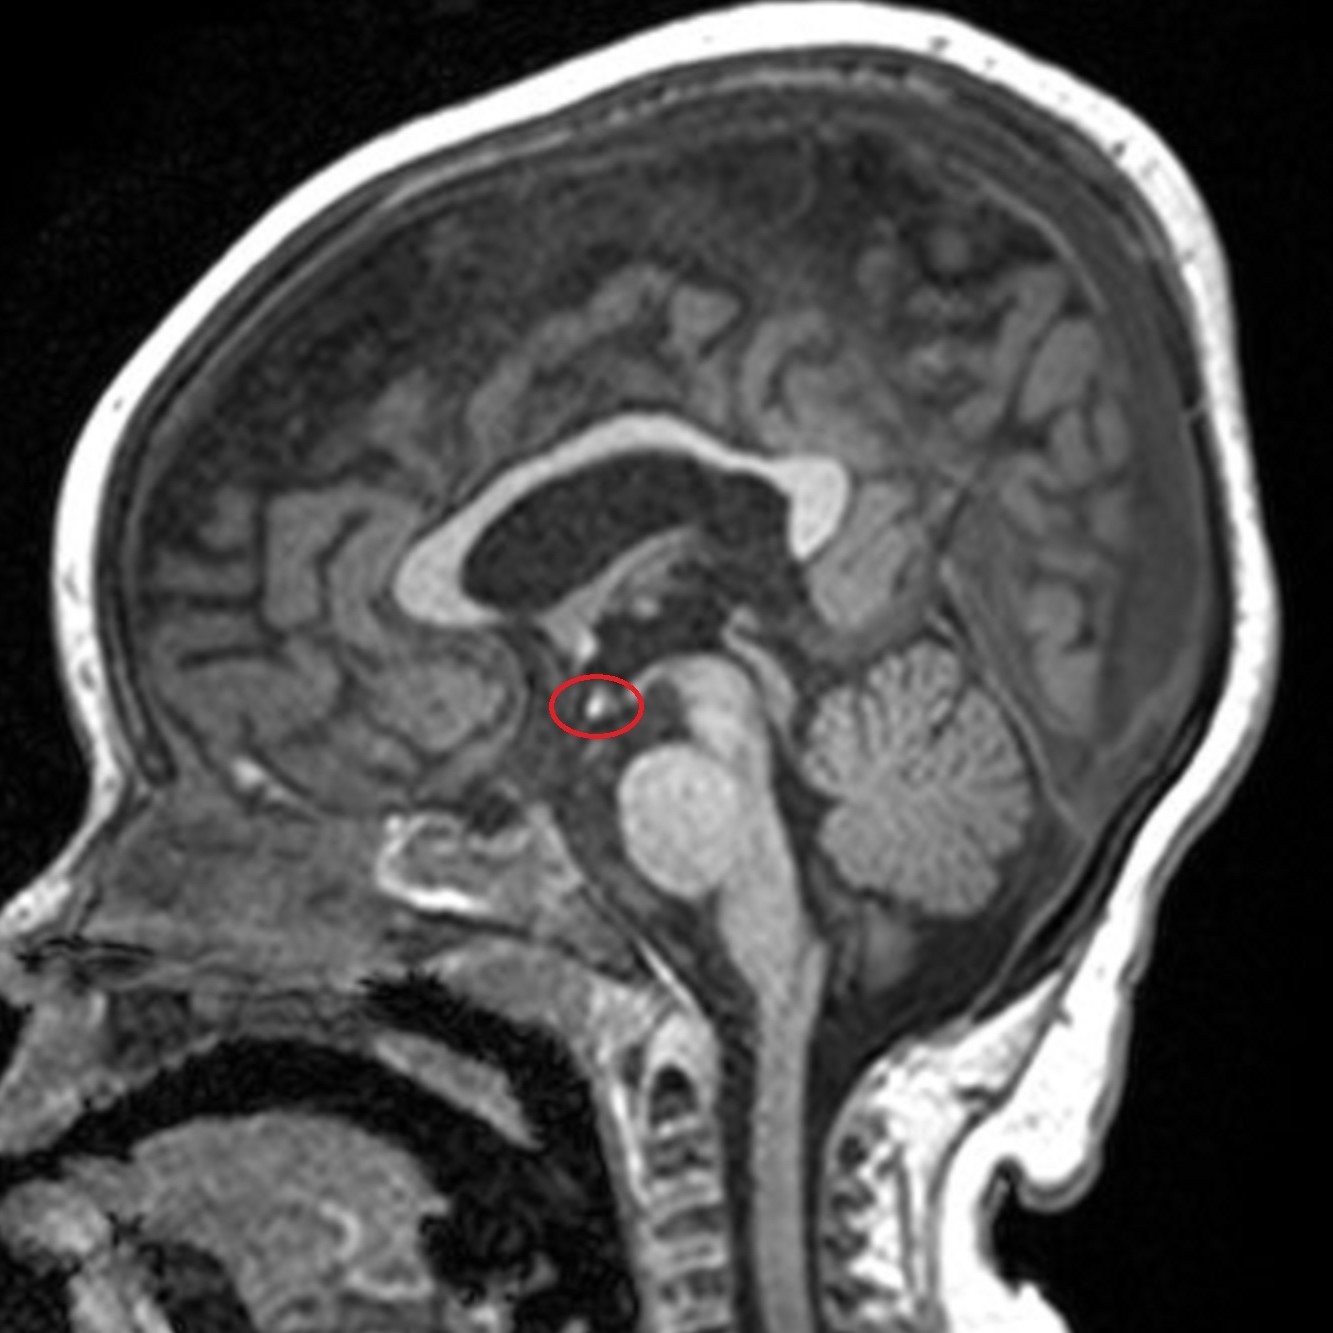

Selected image of sagittal T1-weighted sequence showed the ectopic posterior pituitary gland at the roof of the third ventricle (red circle).

Hypoplastic optic nerves and chiasm, absence septum pellucidum with resultant typical configuration of the anterior horns of the lateral ventricles, along with ectopia of the posterior pituitary gland. On the other hand, the globes are intact and the olfactory bulbs are present with no evidence of associated parenchymal abnormality.